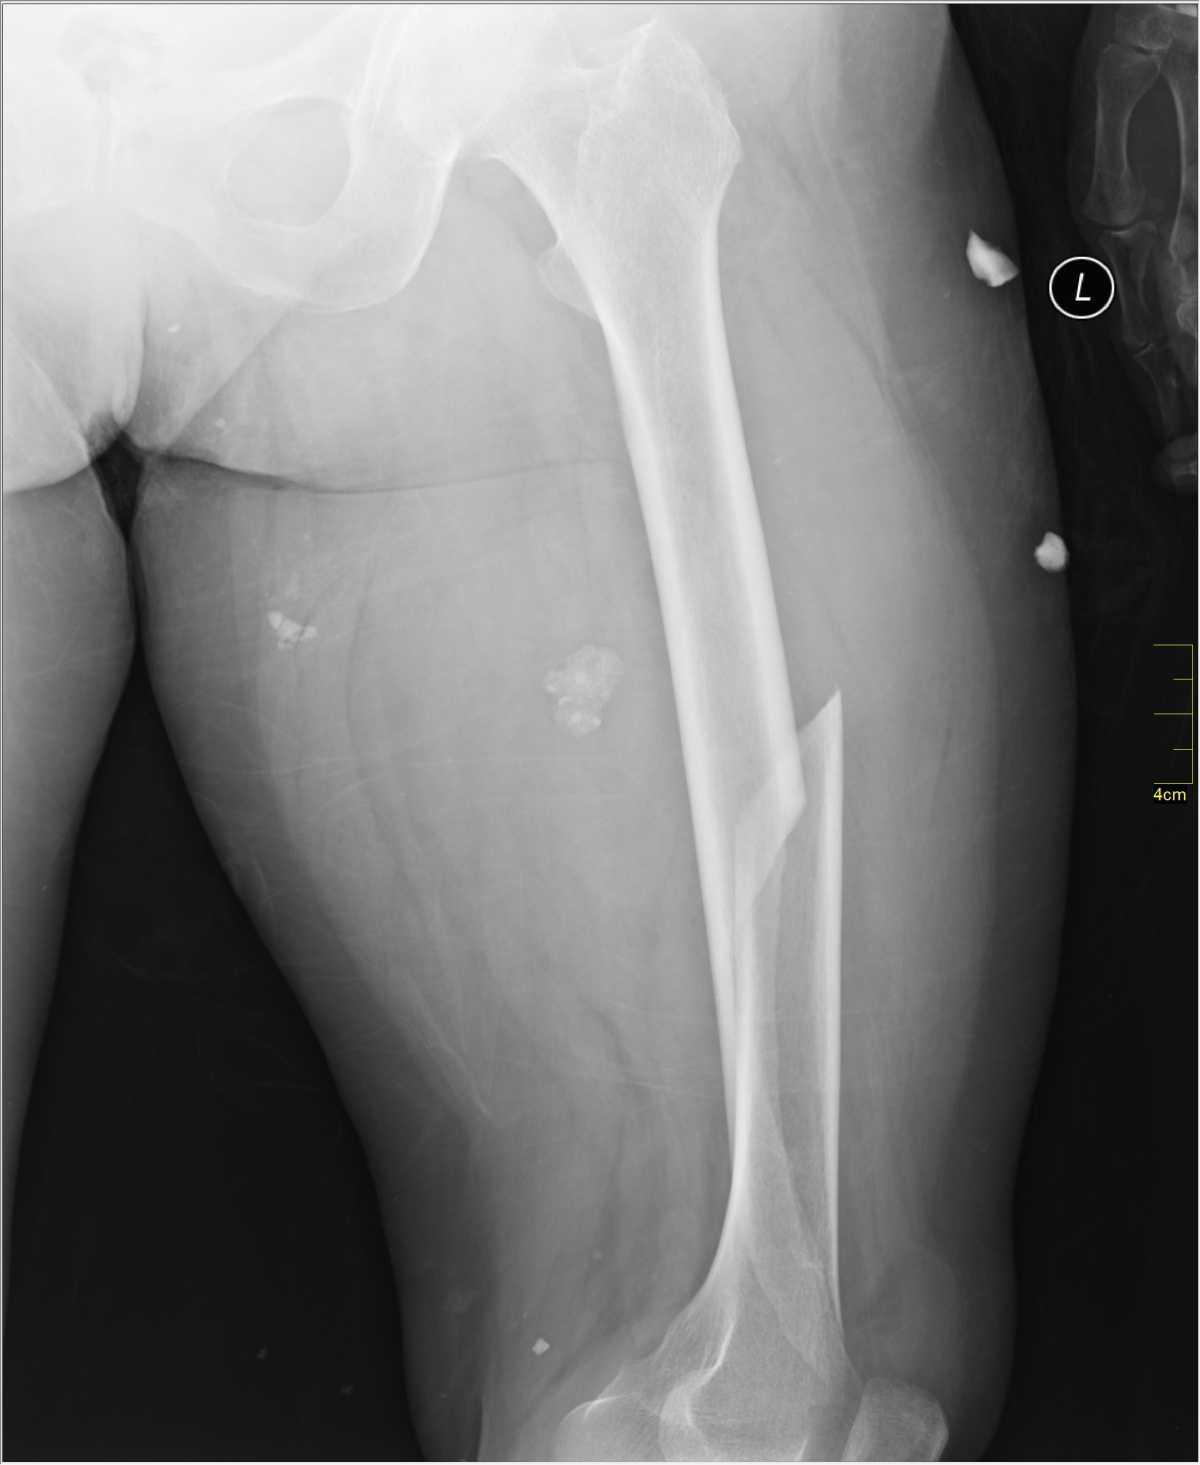

Fracture de la diaphyse femorale

Risque de pertes sanguines et d’embolie graisseuse.

→ Traitement chirurgical.